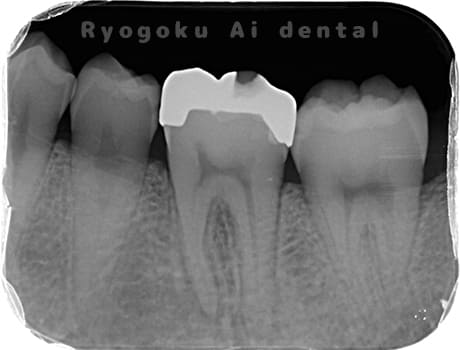

Case04

-

- 原因

- 慢性根尖性歯周炎

- 治療期間

- 3ヶ月

- 治療内容

- マイクロエンド

- 治療費用

- 121,000円

噛むと痛みが出る、とのことで来院した患者様です。他院での根管治療を終えてましたが、根尖病変を認めるため、マイクロエンドを行いました。

<リスク・副作用>

術後は痛み、腫れ、痺れなどの副作用が生じる場合があります。症状が再発する可能性があります。